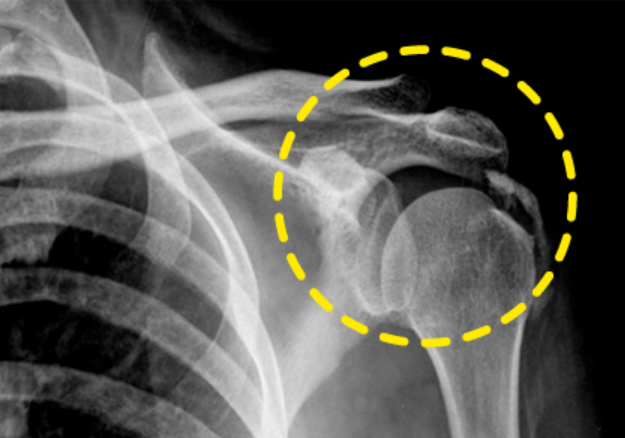

어깨통증 원인 4. 석회성 건염

어깨통증 원인 네 번째는 석회성 건염입니다. 석회성 건염 역시 지속적인 통증보다는 갑작스럽게 어깨 부위에 심한 통증이 느껴질 때 의심할 수 있습니다. 이 때는 밤잠을 이룰 수 없을 정도로 고통을 주는데 보통 노화나 순환 장애로 어깨 부위 특히 힘줄에 칼슘이 축적되며 힘줄과 주변 조직에 통증을 유발하게 됩니다. 질병의 증상은 다양한데 해당 부위를 누르는 경우 심한 통증이 느껴진다면 우선적으로 석회성 건염일 가능성이 높으며 이때도 초음파 촬영이나 X레이 검사를 실시합니다.

석회성 건염 치료는 증상이 심하지 않으면 약물이나 주사치료, ·온찜질, 물리치료(체외충격파) 등 비수술적 치료를 우선적으로 실시하며 이러한 방식으로도 통증이 완화되지 않는다면 석회를 제거하는 관절경 수술을 동반합니다. 따라서 여러 이유로 발생하는 어깨통증 원인에 대해 이해를 하시고 가까운 전문병원을 찾아 진단을 받으신 후 증상에 맞는 치료를 받으시기 바랍니다.